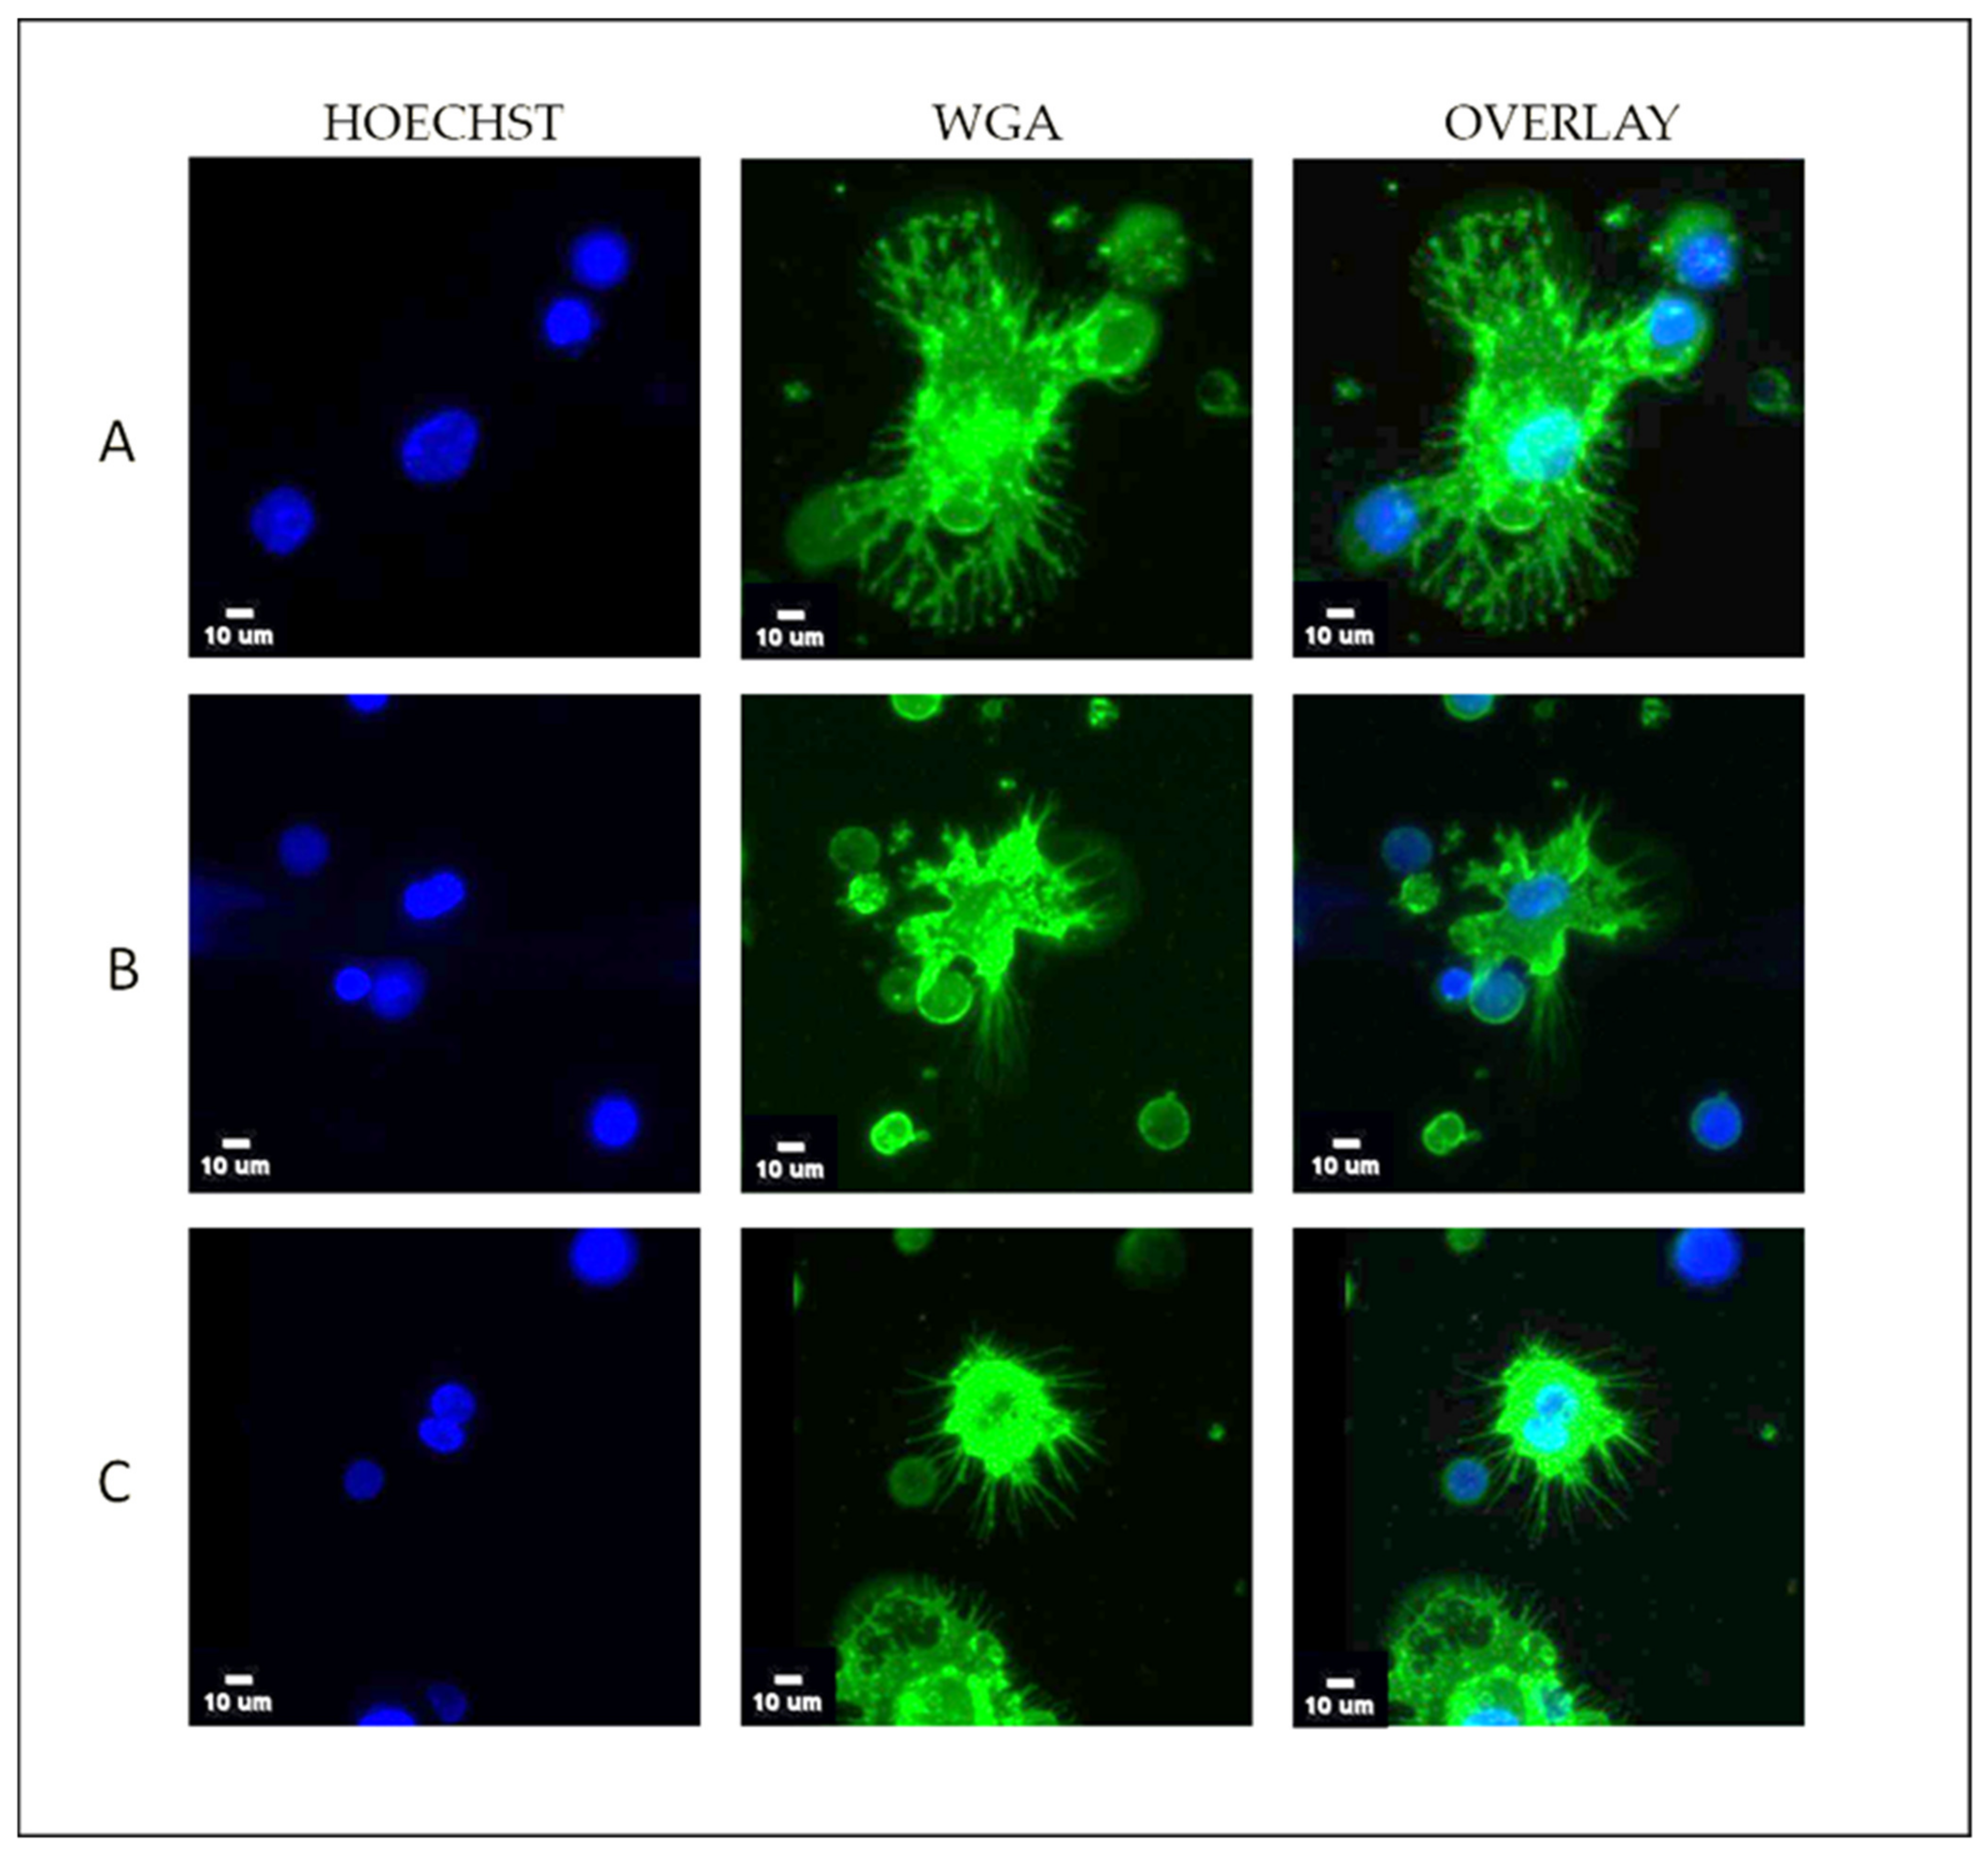

3.1. TetherChip Analysis of Cancer Cell Lines and Live CTCs